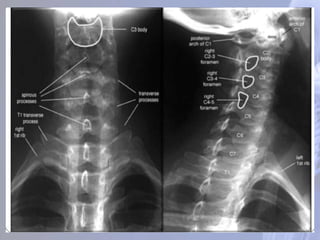

Região cervical (CI– CVII) Os processos espinhosos de C1-6 freqüentemente são bífidos; Todas as vértebras cervicais possuem três forames: um forame vertebral e dois forames transversários

CIII - CVI Sãosimilares as vértebras cervicais típicas descritas anteriormente . Processo espinhoso curto bífurcado Face articular superior Pedículo corpo De forma triangular

CERVICAL (C7) Apresenta umgrande processo espinhoso que pode ser visto e palpado na base da nuca. Processo transverso Sulco do nervo espinhal Forame do processo transverso Face articular superior Forame vertebral Processo espinhoso Não bifurcado